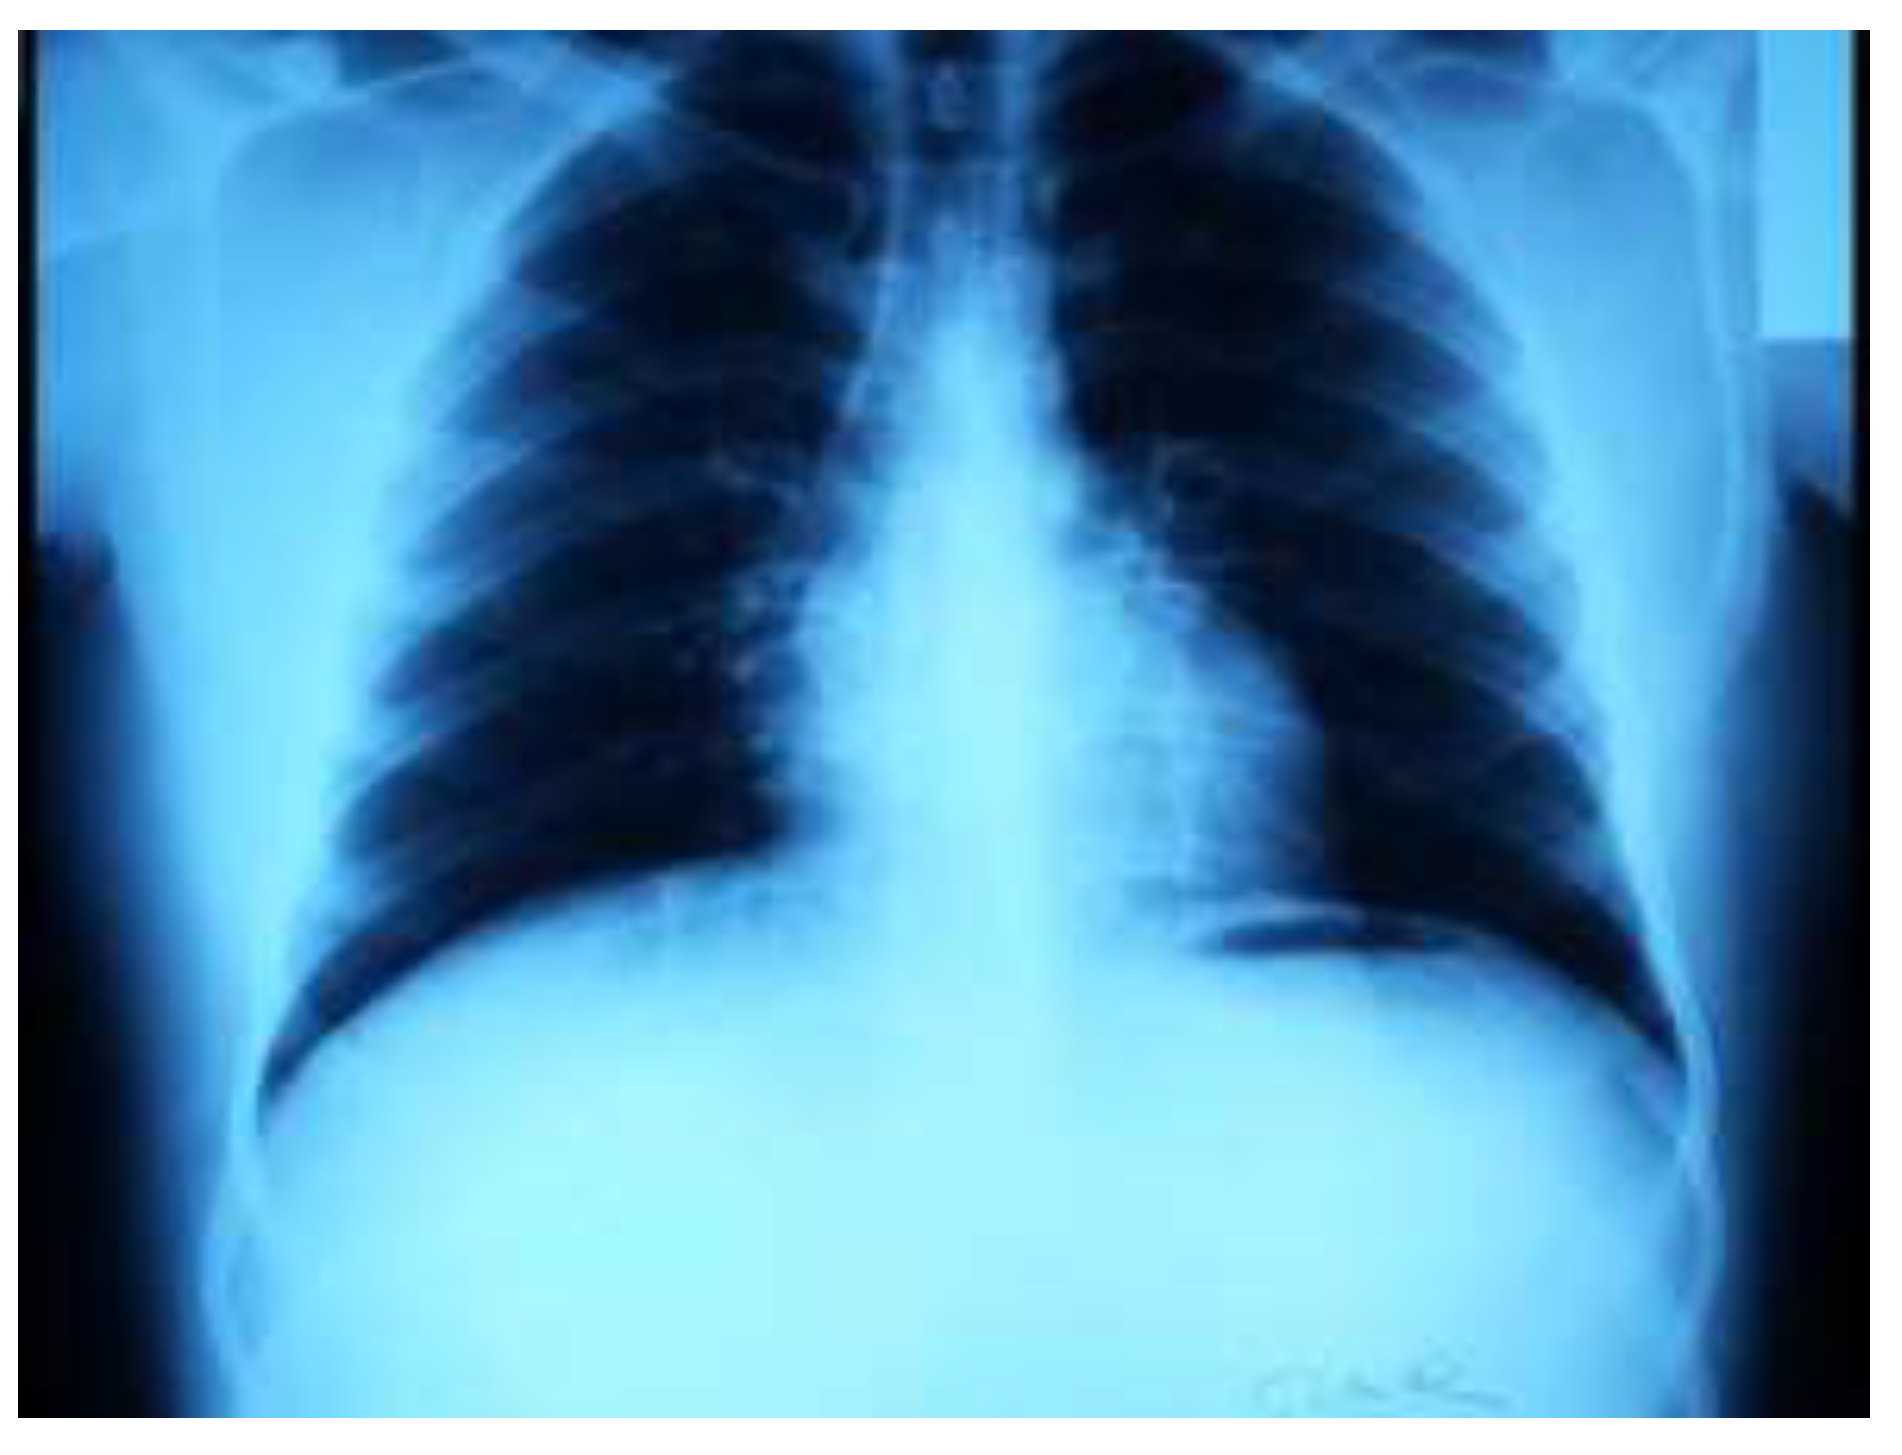

Case Presentation

- Non-ST segment elevation myocardial infarction.

- Incomplete right bundle branch block.